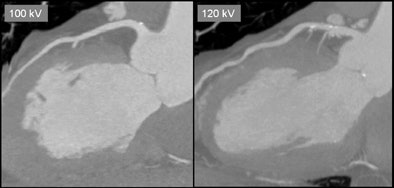

| Curved-planar maximum intensity projections of the left descending artery demonstrate the image quality of the 100-kV (left) and 120-kV protocol (right) at identical window levels. Images illustrate the higher attenuation in the 100-kV scan protocol. All images courtesy of Dr. Jörg Hausleiter. |

"In terms of image quality, the score was very much the same between the two groups," Hausleiter said. Image quality scores for the 120-kV scans were a mean of 3.30 (± 0.6), versus a score of 3.28 (± 0.68) for the 100-kV studies.